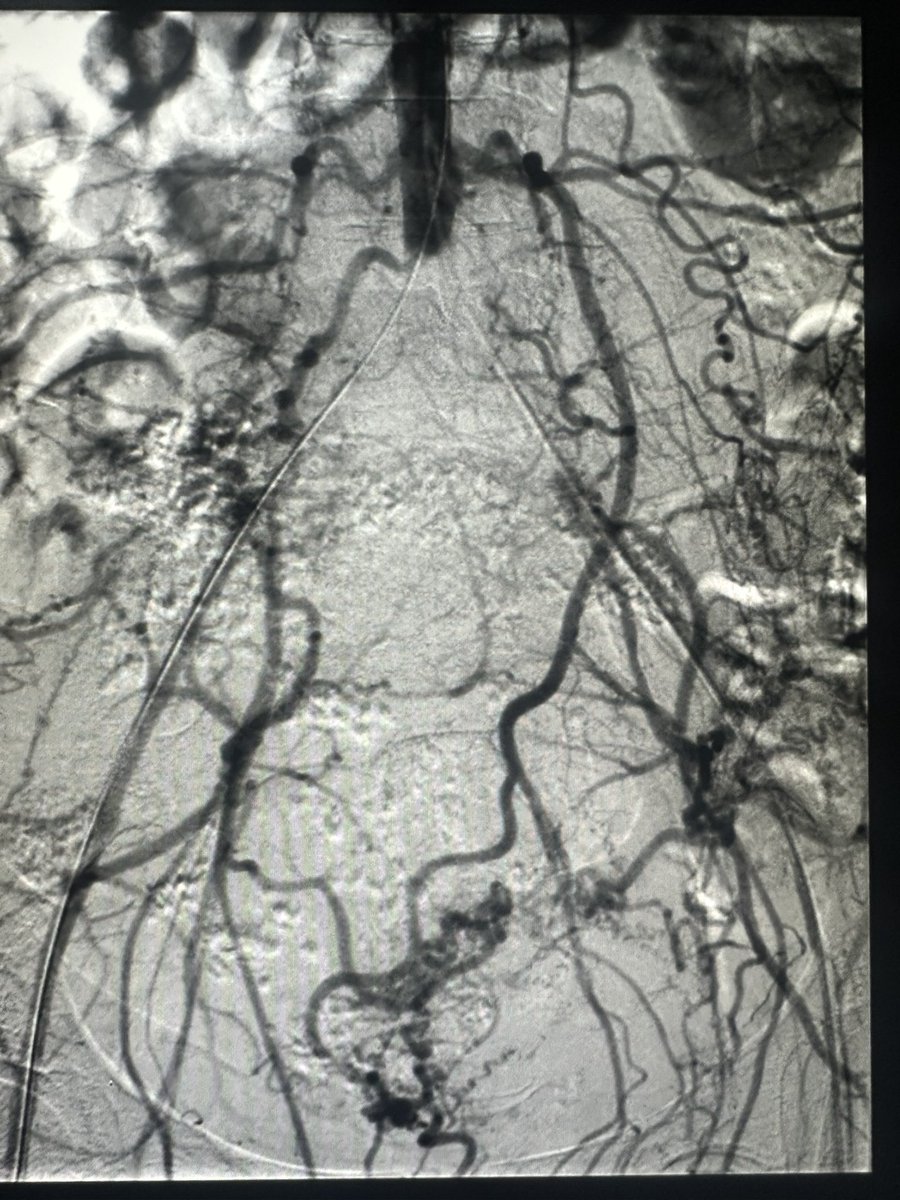

How do you wipe out collaterals? Kiss them goodbye! #irad #vascular #cardiotwitter @VascularSVS @SIRRFS @SIRspecialists @SIR_ECS